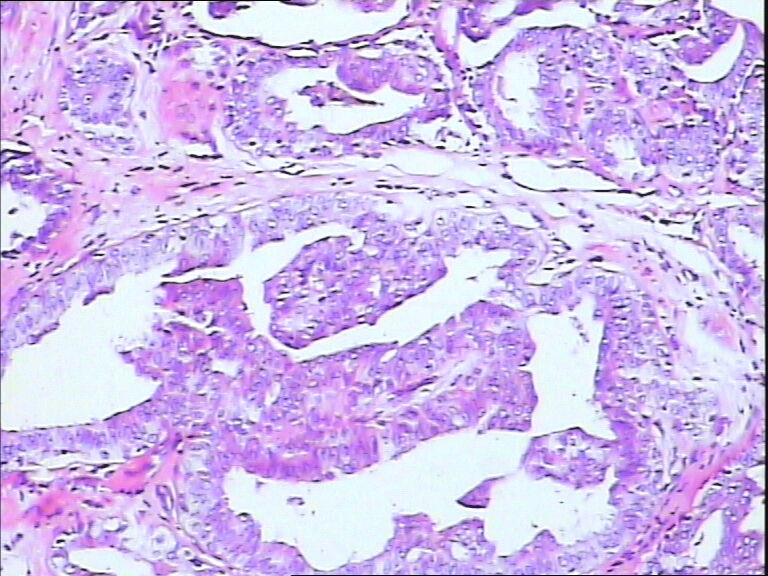

42y

左乳头有3mm结节

灰白不整形组织一块:0.7*0.5*0.4

导管内乳头状肿瘤